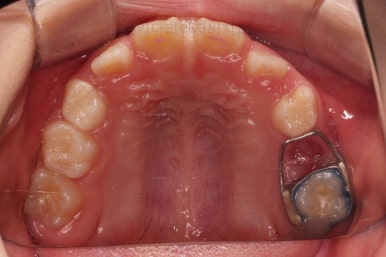

장치 사용 4달째 모습입니다.

벌써 개방교합이 개선되고 있고, 반대교합도 많이 좋아져서 거의 위아래 앞니가 비슷한 위치까지 왔네요.

왼쪽 하단 사진의 어금니에 있는 금속성 장치는 band & loop(밴드 앤 루프)라고 하는 공간유지장치인데요. 오래 써야하는 유치가 일찍 빠지는 바람에 그 공간을 잡아두는 장치입니다.